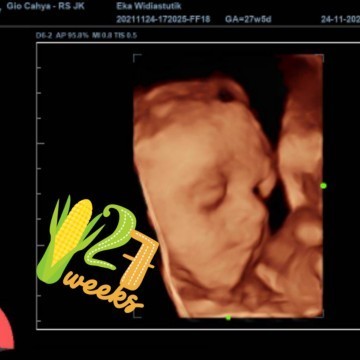

Assalamualaikum bunda smua,ini foto USG janin saya wktu usia kehamilan 27w5d beratnya sdh 1kg2ons,skrng sdh masuk 28w6d..ini kehamilan saya yg ke 2 yg jaraknya dekat yaitu selisih 15bulan dengan yg pertama.. Berbeda sekali hamil pertama dan ke 2 ini.. Yg prtama saya nggk ngrasakan apapun sprti orng hamil smpai² saya sdh masuk 3bulan baru kerasa kalau sedang hamil.. Sedangkan kehamilan ke 2 saya dari awal hamil smpai 3bulan sllu mual muntah pusing Tapi Alhamdulillah setelah 4bulan mulai normal lagi sprti mau makan,suka bau wangi²an semacamnya.. Ada yg sama kah dengan saya hpl 22-2-2022 #hanyaberbagicerita